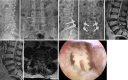

Figures